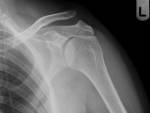

Proximal Humeral fractures

- 2 types of classification:

- Neer Classification. Based on (a)parts fractured rather than the fracture line and (b) extent of displacement

- 1 Part fracture: 80% of proximal humeral fractures. Fracture lines involve 1-4 parts. None of the parts are displaced (i.e <1 cm and <45 degrees)

- 2 Part fracture: fracture lines involve 2-4 parts with 1 part displaced (i.e >1 cm or >45 degrees)

- 4 subtypes of two-part fractures (one for each part):

- surgical neck: most common

- greater tuberosity - frequently seen in the setting of anterior shoulder dislocation. A lower threshold of displacement (>5 mm) has been proposed

- anatomical neck

- lesser tuberosity: uncommon

- 3 Part fracture: fracture lines involve 3-4 parts, with 2 parts displaced (i.e >1 cm or >45 degrees)

- 2 subtypes:

- greater tuberosity and shaft are displaced with respect to the lesser tuberosity and articular surface which remain together

- lesser tuberosity and shaft are displaced with respect to the greater tuberosity and articular surface which remain together

- 4 Part fracture: uncommon. Fracture lines involve more than 4 parts with 3 parts displaced (i.e., >1 cm or >45 degrees) with respect to the 4th

- AO classification, each with subtypes, with the risk of avascular necrosis of the articular surface increasing from A to C:

- type A: extra-articular unifocal (either tuberosity +/- surgical neck of the humerus)

- type B: extra-articular bifocal (both tuberosities +/- surgical neck of the humerus or glenohumeral dislocation)

- type C: extra-articular (anatomical neck) but with compromise to the vascular supply of the articular segment

Management:

- the vast majority of proximal humeral fractures are managed conservatively with supportive sling with physiotherapy to support early (7-10/7) mobilisation

- intervention usually for displaced articular and peri-articular fractures

- most common definition of displacement is ≥1cm between fracture fragments or ≥45° of angulation between fragments